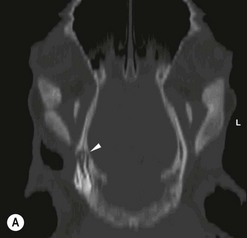

Apical infection (Fig. 13.41)

Both clinical and radiographic signs of periapical (apical) infection are often specific to the tooth involved. For example, the apices of the maxillary 06s and 07s (and variably the 08s) and all the mandibular cheek teeth are contained within thick bone; hence, cases of periapical infection of these teeth typically present with facial swelling, which appears radiographically as bone lucency often surrounded by sclerosis and periosteal new bone formation, and also cutaneous draining tracts. The maxillary 08s–11s apices are contained within the maxillary sinuses; hence, horses with periapical infection of these teeth present clinically with nasal discharge and radiographically with changes associated with both dental infection and secondary sinusitis.

Fig. 13.41 Radiographic signs of periapical infection. (A) Radiolucent halos are evident around both roots of an infected 408, with widening of periodontal space, sclerosis of the ventral mandibular cortex and periosteal new bone deposition. (B) A zone of sclerosis is present around this infected 306. The affected apex is somewhat blunter than those of adjacent teeth; however, this can be a normal feature of 06s. An arrow points to a small radio-opaque marker placed on the skin at the site of facial swelling. (C) Infected 108. A periapical radiolucent halo surrounded by marked sclerosis is evident around the infected apex of this tooth, which lies outwith the rostral maxillary sinus in this horse. (D) Gross destruction of the architecture of this infected 407 dental bud is present, with loss of much of the apical aspect of its crown. Multiple radio-opaque fragments are present in the alveolus, which may represent dental fragments or cementoma formation. A draining tract (with probe inserted) and gross mandibular new bone formation are evident. (E) Marked sclerosis is present around an apically infected 210. This horse had concurrent sinusitis. (F) Massive reactive cementoma deposition is present around the apex of chronically infected 207. Dystrophic calcification of the nasal conchae is likely also contributing to the radio-opaque appearance in the area rostral to the alveolus of 207. Most of the reserve crown of this tooth was still present; however, it is quite radiolucent, due to demineralization caused by chronic infection.

Radiographic changes consistent with early periapical infection include widening of the periodontal space and focal loss or irregularity of the lamina dura. When periapical infection has been present for many weeks, the affected apex and adjacent alveolar bone develop lytic changes, especially in mature teeth where the true roots (non-enamel areas) are well formed, due to decalcification and/or destruction of dental and adjacent alveolar tissues. These changes manifest as periapical radiolucent ‘halos’, and with time, a rounded or ‘clubbed’ appearance of the tooth roots can develop due to gross lysis/destruction of the root structures. In more chronic periapical infection, a zone of radiodense sclerosis may surround the periapical ‘halo’, due to new bone deposition around the lytic infected dental/alveolar area. More marked sclerosis develops around the apices of the rostral maxillary and mandibular cheek teeth than around the apices of the caudal maxillary cheek teeth, because the apices of the former teeth are positioned in denser bone than those of the caudal maxillary cheek teeth, which are situated in only thin alveolar bone within the maxillary sinuses.